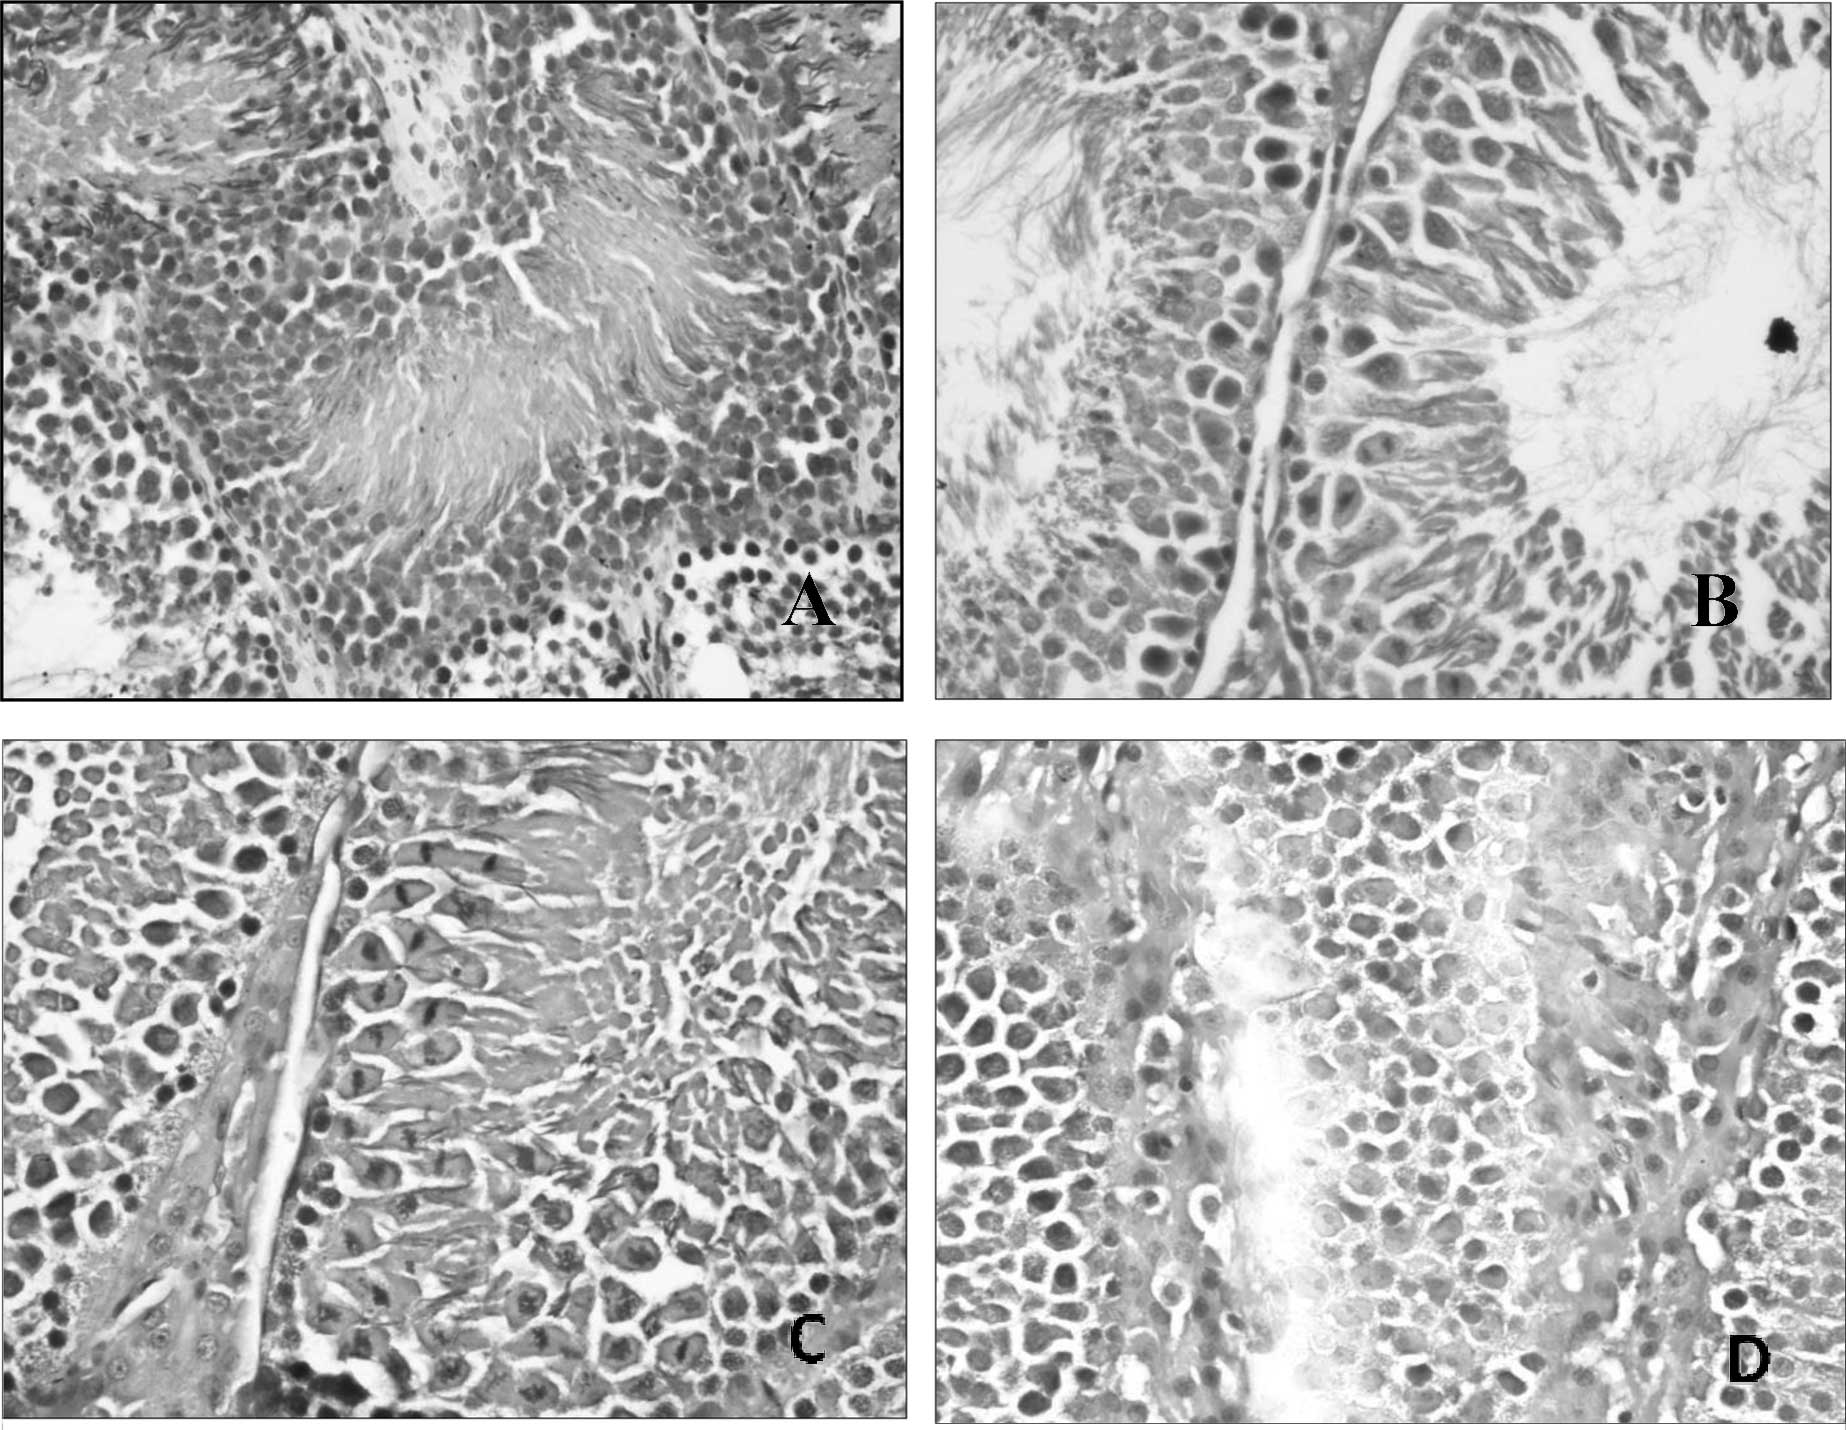

Histopathological alterations noted under the microscope included shrunken seminiferous tubules, decreased cellularity with reduction in matured forms when compared to immature forms, suggesting a maturation arrest, thickening of basement membrane, fibrosis affecting both the basement membrane and the interstitium (Fig. 1). Our findings are consistent with other studies (22,23), in which many changes were observed after lead administration for 30 days, including shrunken seminiferous tubules with a wavy outline, thickened basement membrane with hyalinization, maturation arrest with abnormal ratio of spermatogenic cells and also abnormalities in interstitial Leydig cells.

Figure 1.

Photomicrograph of testicular tissue from (A) the lead acetate group showing thickening of basement membrane with fibrosis affecting the lumen and an area of central necrosis (magnification, ×200; H&E); (B) the Etlingera elatior group showing healthy testicular tissue with abundant mitotic spermatogenic cells (magnification, ×400; H&E); (C) the concurrent treatment group showing healthy testicular tissue with abundant mitotic spermatogenic cells (magnification, ×400; H&E); (D) the post-treatment group showing mild thickening of basement membrane and increased interstitial tissue (magnification, ×400; H&E).

In the Etlingera elatior alone group, normal spermatogenesis was noted to be actively ongoing (Fig. 1B) with abundant mature spermatozoa formed. However, it was also noted that the interstitial tissue was increased with certain areas of interstitial oedema, suggesting that Etlingera elatior promotes the growth of interstitial tissue. In the concurrent treatment group, the histology of the testicular tissue was similar to the Etlingera elatior alone group, with normal spermatogenesis (Fig. 1C) noted and abundant mature spermatozoa formed. There was also an increased interstitial tissue observed, but in addition to that, congestion of blood vessels was also noted and a moderate thickening of the basement membrane. This suggests that Etlingera elatior protects the testicular tissue with only minor changes occurring. In the post-treatment group, normal architecture of seminiferous tubules was noted, with actively ongoing spermatogenesis. However, it was observed that there was mild thickening of the basement membrane (Fig. 1D), increased interstitial tissue with abundant Leydig cells, congestion of blood vessels and the presence of few macrophages in some of the seminiferous tubules. The testicular tissue in this group, although showing all the above-mentioned minor changes, generally appeared healthy, showing that the damage that lead had caused was repaired by the Etlingera elatior post-exposure to lead acetate. The presence of macrophages again was deduced to aid in removing excessive lead present in the testicular tissue. The Etlingera elatior followed by the lead acetate group, on the other hand, appeared to sustain more damage than the two treatment groups. Moderate thickening of the basement membrane was noted with some areas of interstitial oedema (Fig. 1D), and a paucity of cells also suggest that there was a maturation arrest of spermatogenic cells. There was also some congestion of blood vessels noted. Collectively, the tissues appeared to be mild to moderately atrophic, confirming with the biochemical tests that Etlingera elatior administered prior to lead acetate administration is not as beneficial as a treatment. Again, comparison to other studies was not possible due to the lack of studies on the effect of Etlingera elatior against lead toxicity in the testis. However, our result is still supported by the fact that Etlingera elatior contains a high level of anti-oxidant activity (24), bringing about the promising result obtained.